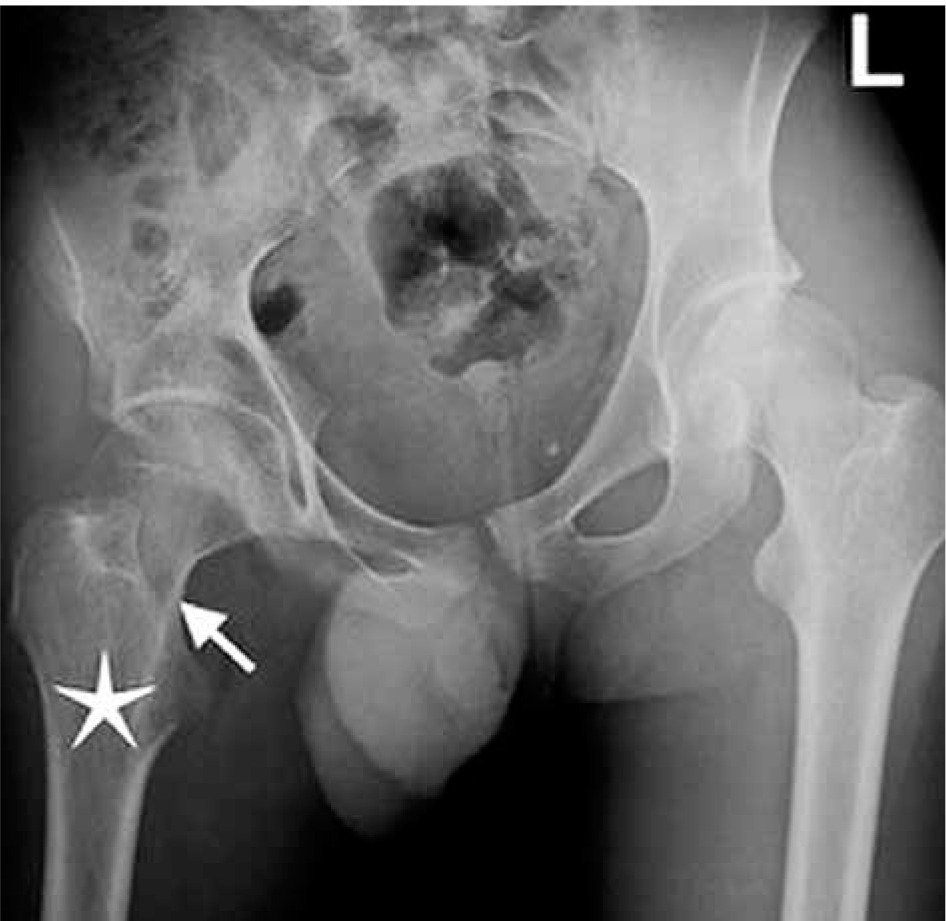

Figure 3

A 16-year-old boy presenting with gait disorder who had 4-year history of hip pain that worsened on nights and was relieved with aspirin. Anteroposterior radiograph image of pelvis demonstrates barely defined lucent nidus (arrow) with a thin peripheral sclerosis in neck of right femur. Note osteopaenia in right femur and right iliac bones and relative (compared to left extremity) hypodensity of thigh muscles due to atrophy. Right femur head is below the horizontal line compared to left side